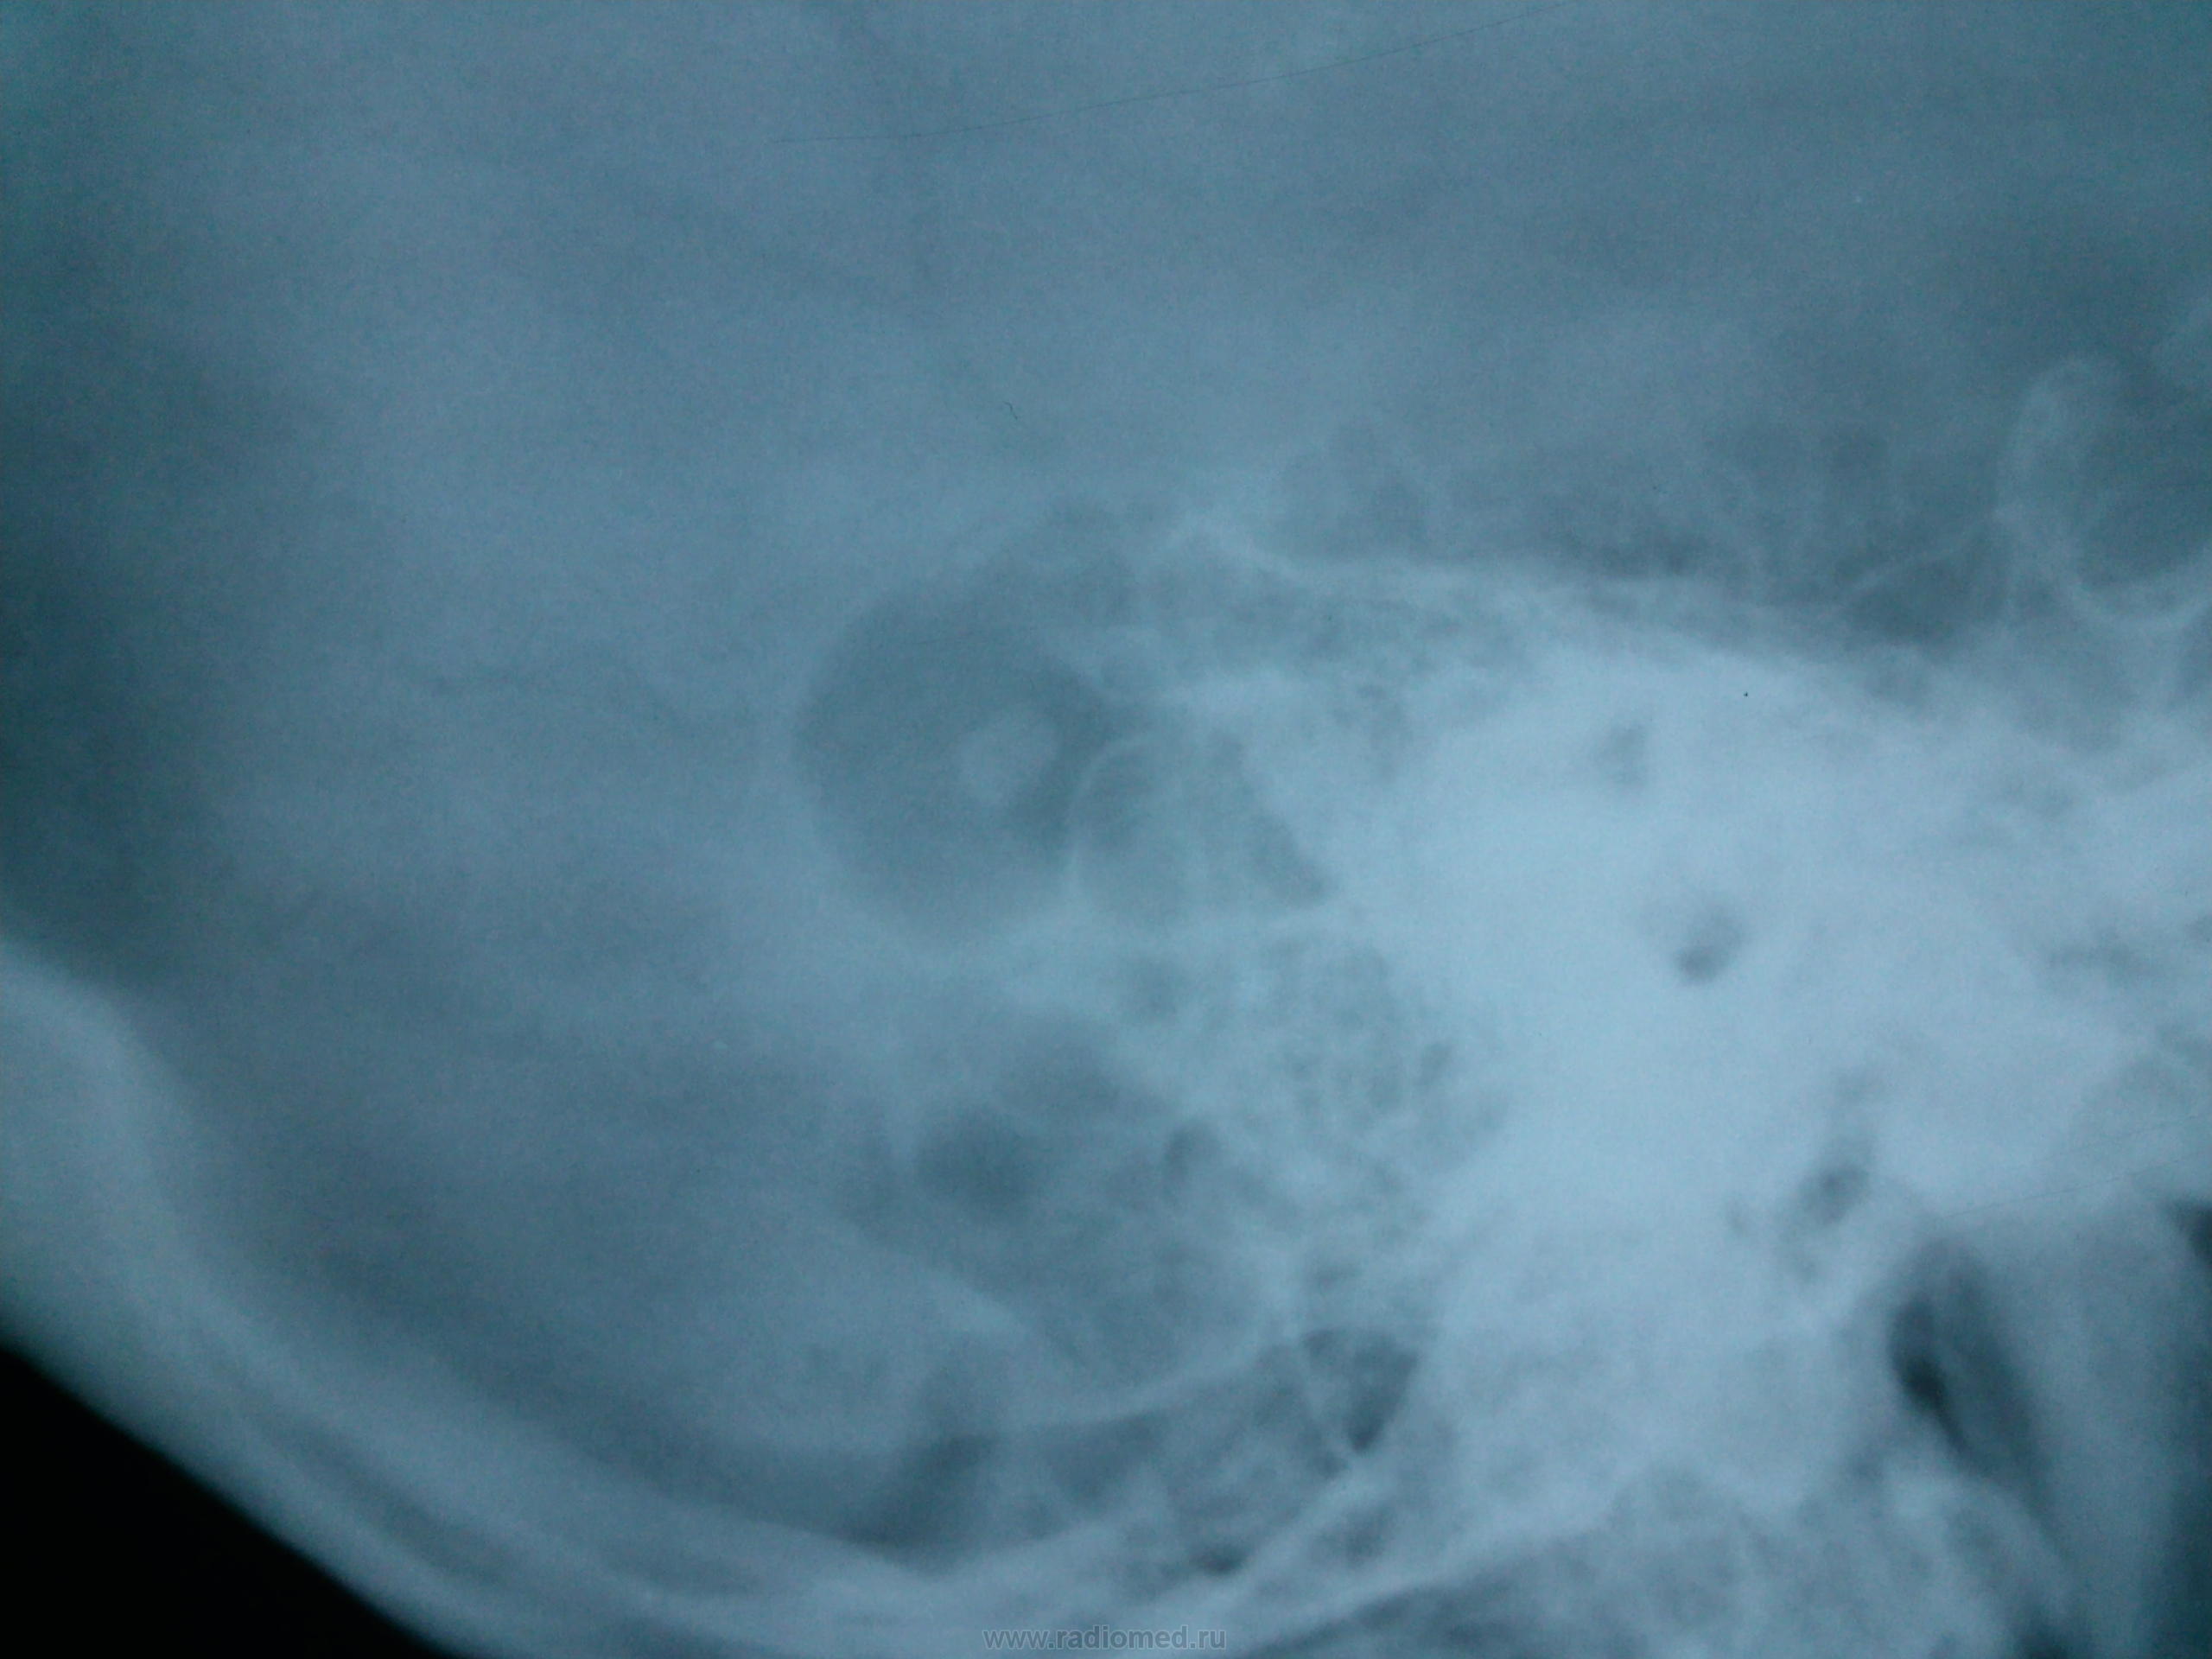

Пол пациента: Женский пол Тип патологии: Инфекция Область исследования: Череп и головной мозг Методы исследования: Rg Что это может быть? https://radiomed.ru/sites/default/files/styles/case_slider_image/public/user/134/foto0002.jpg?itok=rj0nO1qa https://radiomed.ru/sites/default/files/styles/case_slider_image/public/user/134/foto0003_001.jpg?itok=SAI4mEq1 ID:27007 Втр, 12/03/2013 - 23:00 #1 алкс Не на сайте Был на сайте: 10 лет 1 месяц назад Зарегистрирован: 24.10.2012 - 22:55 Публикации: 2915 Какая-то эндоуральная барабашка, с пластикой иль нет, но повреждение сосцевидного отростка фрезой видно. Возможно после гнойного эпитимпанита. Втр, 12/03/2013 - 23:18 #2 И.Бондаренко Не на сайте Был на сайте: 2 дня 16 часов назад Зарегистрирован: 13.09.2011 - 22:55 Публикации: 9206 Может быть ячейка сосцевидного отростка такая? Не пробовали смотреть скопически или косые снимки? Ср, 13/03/2013 - 01:29 #3 Алексей Игореви... Не на сайте Был на сайте: 6 лет 11 месяцев назад Зарегистрирован: 08.08.2012 - 21:52 Публикации: 786 По очертаниям подходит по ячейку. Вот какое происхождение секвестра внутри нее? Возможно и дефект посттраматический. "Обучая других - учишься сам". Н.И.Пирогов Ср, 13/03/2013 - 05:31 #4 ЧЮГ Не на сайте Был на сайте: 3 месяцев 2 недели назад Зарегистрирован: 31.10.2012 - 15:10 Публикации: 414 Прямая р-гр. срезана - похоже с левой стороны такая же ячейка. Ср, 13/03/2013 - 17:23 #5 Пантелеймон Не на сайте Был на сайте: 7 лет 8 месяцев назад Зарегистрирован: 16.07.2010 - 14:58 Публикации: 63 Холестеатома. А анамнез, клиника? Ср, 13/03/2013 - 17:30 #6 Фил Не на сайте Был на сайте: 6 лет 10 месяцев назад Зарегистрирован: 13.09.2011 - 16:24 Публикации: 137 А жалобы - есть ? Для холестеатомы локализация и проекция не подходящая . Ср, 13/03/2013 - 23:58 #7 brainmodel Не на сайте Был на сайте: 3 месяцев 1 неделя назад Зарегистрирован: 18.03.2010 - 22:04 Публикации: 2881 Этот "глаз" расположен кзади от углов Чителли обеих височных костей, так что ни под холестеатому, ни под фрезевое ложе не подходит. Варианты: - предоставить нормальную прямую проекцию (для начала) - прямое показание для снимков по Шюллеру и Майеру - достать пациента и выяснить анамнез, можно и прощупать интересующие области Без первых двух условий гадать можно много... Verum plus uno esse non potest.

Какая-то эндоуральная барабашка, с пластикой иль нет, но повреждение сосцевидного отростка фрезой видно. Возможно после гнойного эпитимпанита.

Может быть ячейка сосцевидного отростка такая? Не пробовали смотреть скопически или косые снимки?

По очертаниям подходит по ячейку. Вот какое происхождение секвестра внутри нее? Возможно и дефект посттраматический.

Прямая р-гр. срезана - похоже с левой стороны такая же ячейка.

Холестеатома. А анамнез, клиника?

А жалобы - есть ? Для холестеатомы локализация и проекция не подходящая .

Этот "глаз" расположен кзади от углов Чителли обеих височных костей, так что ни под холестеатому, ни под фрезевое ложе не подходит. Варианты:

- предоставить нормальную прямую проекцию (для начала)

- прямое показание для снимков по Шюллеру и Майеру

- достать пациента и выяснить анамнез, можно и прощупать интересующие области

Без первых двух условий гадать можно много...